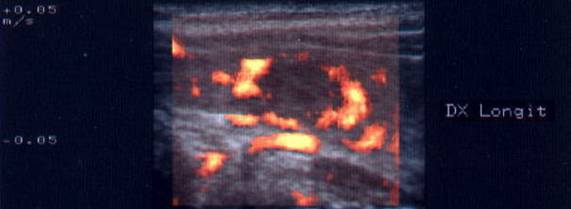

Femeie de 34 ani. Gusa nodulara in tratament supresiv cu tiroxina. Durere intensa laterocervical dreapta, cu evidentierea unei tumefactii dureroase la palpare.

Formatiunea nodulara are margini neregulate, de 22x21x23mm (5,7 cc), marcant hipoecogena, cu stratificari de ecouri spre versantul posterior. Nodulul nu era prezent in ecografia efectuata in urma cu 4 zile.

Aceeasi pacienta. Absenta vascularizatiei in interiorul nodulului, atat la doppler color cat si in powerdoppler; se evidentiaza un vas care decoleaza marginea inferioara a nodulului.